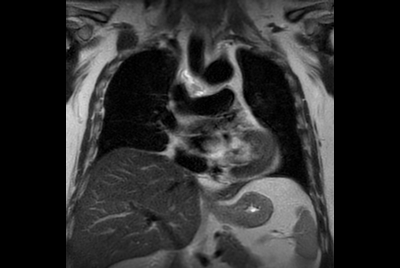

Chest overview